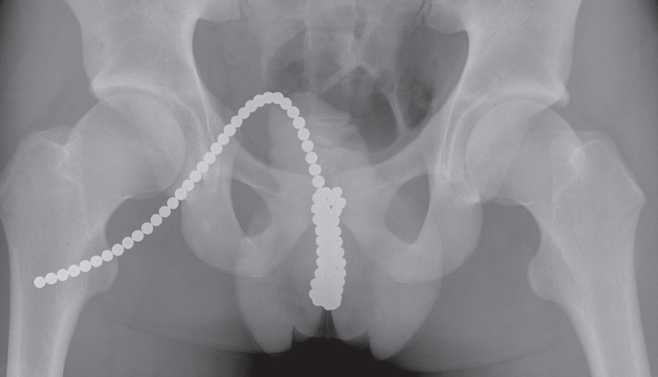

Lawrence M. Wyner, MD

A 17-year-old young man presented to the emergency department shortly after inserting several dozen Buckyballs into his urethra, presumably for self-stimulation purposes.